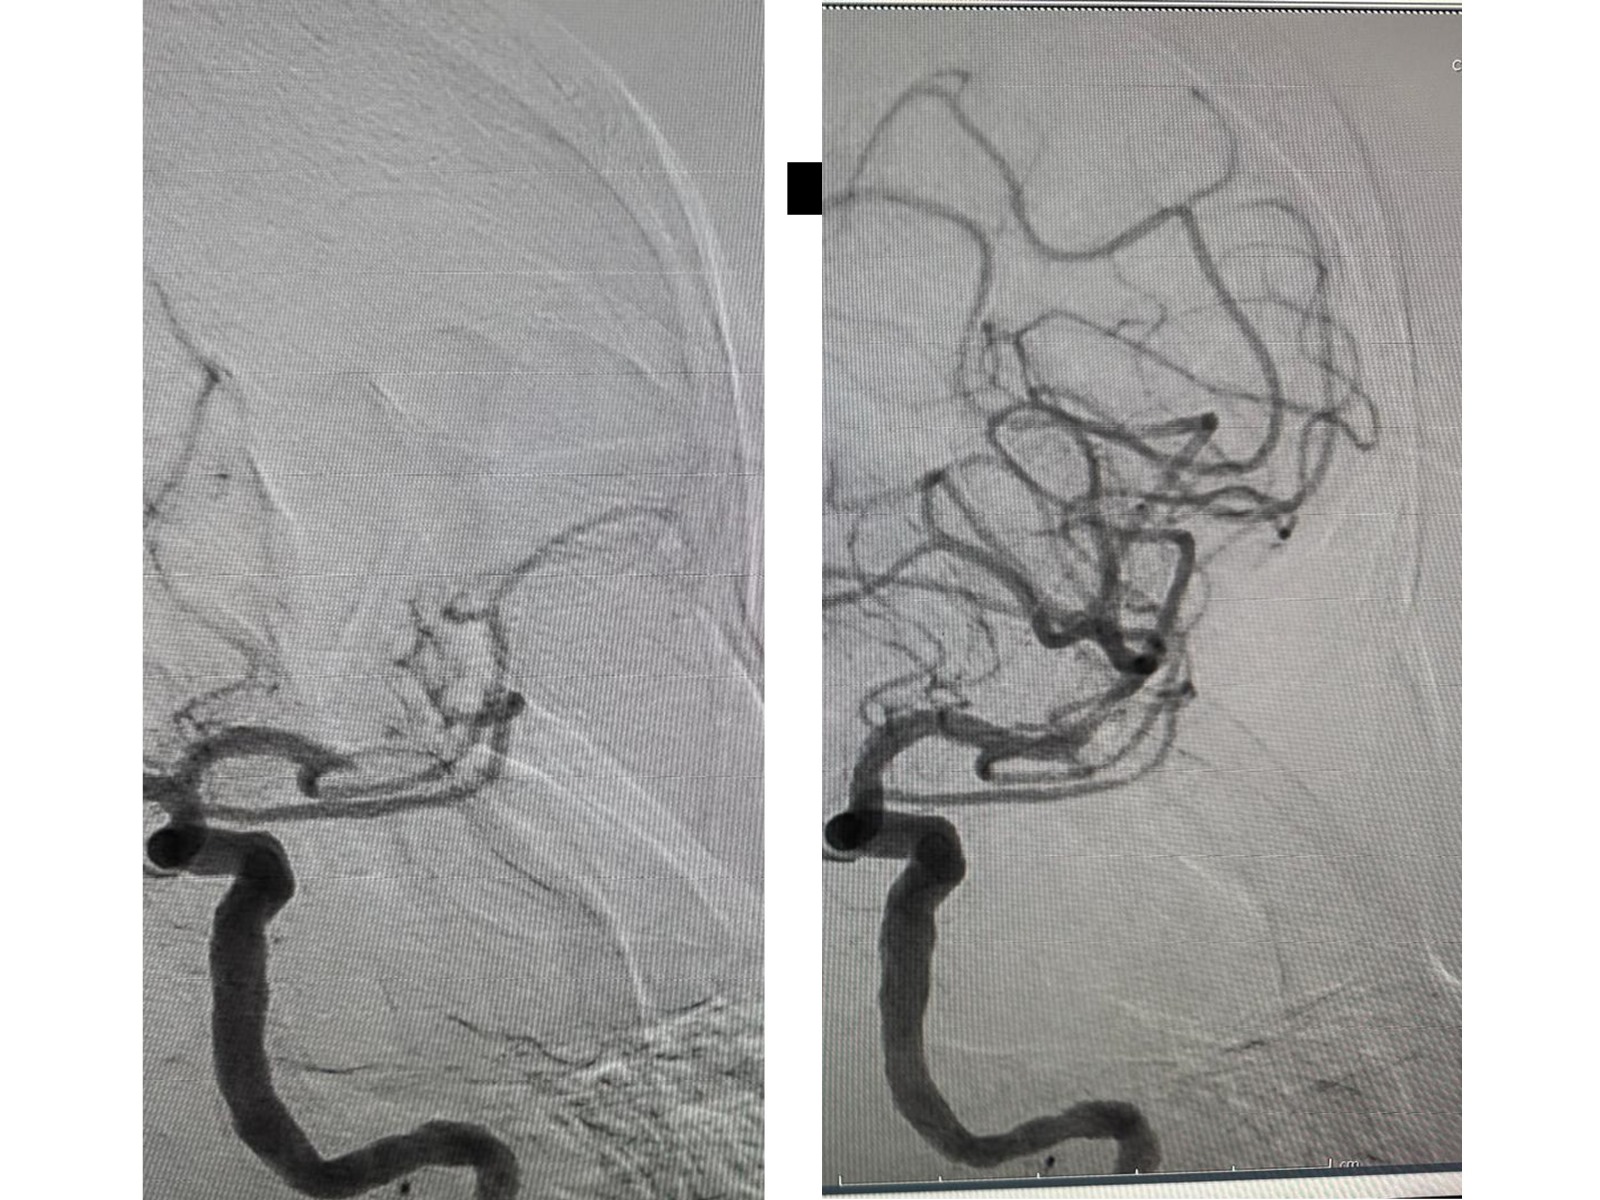

Dr. Mihály István kiemelte: nem volt könnyű a beavatkozás, többszöri próbálkozásra sikerült eltávolítaniuk a vérrögöt és „rekanalizálni” az osztóeret. A beteg pár órán belül jobban lett, kezét, lábát emelni tudta, beszélni kezdett, magához tért. A szakember hangsúlyozta: ha nem tudták volna elvégezni a beavatkozást, a páciens valószínűleg súlyos állapotban maradt volna.

„A beavatkozást angiográfon végeztük, ami egy speciális röntgengép, amin mostanáig a kardiológus kollégák dolgoztak a kórházban, és csak a kardiointervenciókat végezték. Ez azért szükséges, hogy át tudjuk világítani a paciens testét, és lássuk csak az ereket, amikben mi a katéterekkel járunk. A beteg ma jól van, úgyhogy egy jól sikerült beavatkozás volt, és viszonylag rövid időn belül sikerült ezt elvégezni” – osztotta meg dr. Mihály István.